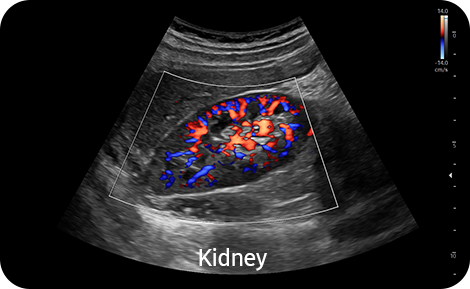

Show blood flow in vessels

in a 3D like display

LumiFlow™ ¹ is a function that visualizes blood flow in 3 dimensional-like to help understand the structure of blood flow and small vessels intuitively.

Examine peripheral vessels with

directional power Doppler

S-Flow™, a directional Power Doppler imaging technology, can help to detect even the peripheral blood vessels. It enables accurate diagnosis when the blood flow examination is especially difficult.